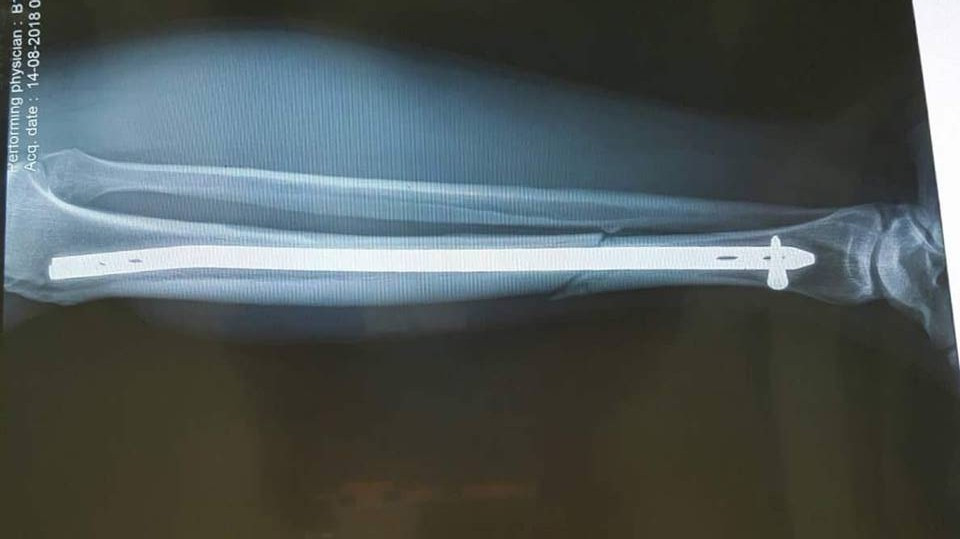

| Phim chụp X-Quang sau phẫu thuật của anh Tuyền. |